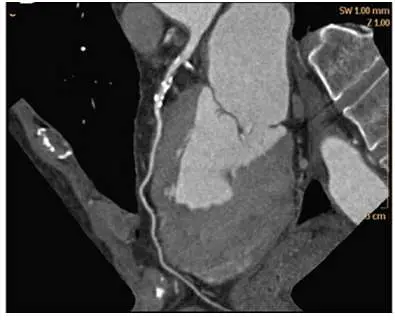

如圖所示的 CT 影像是採用何種技術所產生的

Amaximum intensity projection(MIP)

Bshaded surface display(SSD)

Cmulti-planar reformation(MPR)

Dvolume rendering(VR)

本題提供的圖片為一張心臟電腦斷層的後處理影像,具備以下視覺與解剖特徵:

- 影像特徵:畫面中顯示一條充滿對比劑的管腔結構(冠狀動脈,依其解剖位置與右心室的相對關係,推測為右冠狀動脈 RCA),且血管壁上帶有多處高密度的鈣化斑塊 (calcified plaques)。

- 空間呈現:冠狀動脈在 3D 解剖空間中原為彎曲的立體走向,但在這張影像中卻被「拉直」並完整顯示在同一個 2D 平面上。

- 組織對比:除了血管本身,還能清晰看見周圍軟組織(如心肌、心室腔室)的原始灰階斷面結構,且影像右上角標示著「SW 1.00 mm」(Slice Width,切面厚度),符合 2D 切面影像的特性。 綜合以上特徵,此為典型的「曲面重組」(Curved Planar Reformation, CPR) 影像,而 CPR 正是多重平面重組 (Mul